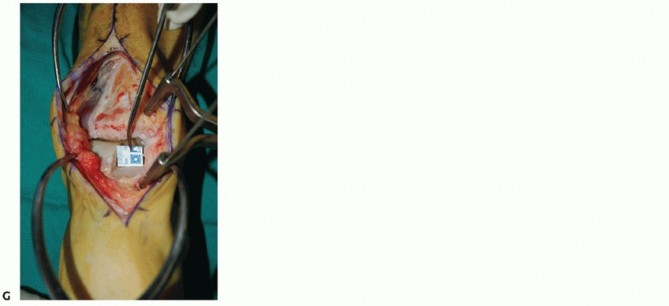

- TECH FIG 1 • (continued) G. Fluoroscopic image showing near-complete bone cut. H. Release of posterior tibial tendon sheath from distal medial malleolus to allow mobilization.

- TECH FIG 2 • A,B. Identifying the extent of the talar shoulder lesion. (continued)

- TECH FIG 2 • (continued) C-E. Excision of the talar shoulder lesion using the microsagittal and oscillating saws. F. Talar shoulder lesion removed.